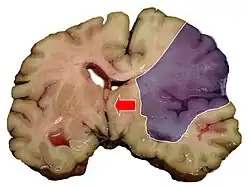

Einteilung nach Infarktmuster in der Bildgebung

Es kann zwischen Territorialinfarkten, Grenzzoneninfarkten und lakunären Infarkten unterschieden werden.

Territorialinfarkte entstehen durch embolischen Verschluss hirnversorgender Arterien und betreffen das Versorgungsgebiet (Territorium) des Gefäßes. Lakunäre Infarkte sind kleiner als 1,5 cm. Sie entstehen meist durch mikroangiopathische Veränderungen. Grenzzoneninfarkte sind hämodynamischer Genese. Sie entstehen meist durch Verschluss der großen extrakraniellen Gefäße oder durch einen passageren Blutdruckabfall bei vorbestehenden Einengungen der Halsschlagadern.[9]